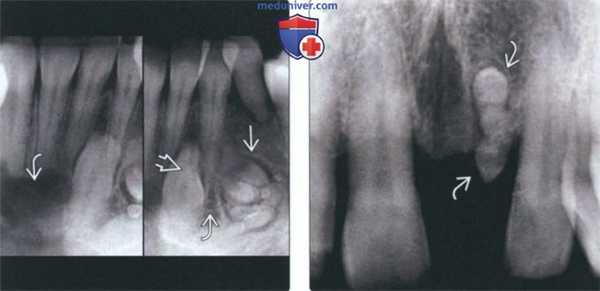

(Слева) На панорамной реформатированной КЛКТ определяется составная одонтома в области корня полностью прорезавшегося постоянного левого клыка нижней челюсти. Обратите внимание на кортикальную пластинку на периферии и гиподенсный ободок изнутри от нее.

(Справа) На аксиальной КЛКТ у этого же пациента определяется вздутие и истончение язычной и лицевой кортикальных пластинок нижней челюсти в области составной одонтомы. От корня постоянного клыка одонтома отделена тонким просветлением.

(Слева) На периапикальных рентгенограммах передних отделов нижней челюсти определяется одонтома возле импактного клыка нижней челюсти слева. Просветление, связанное с клыком, - подтвержденная одонтогенная кератокиста. Одонтомы часто могут обнаруживаться в сочетании с другими поражениями.

(Справа) На периапикальной рентгенограмме определяется агенезия постоянною центрального резца верхней челюсти слева с формированием частично прорезавшейся составной одонтомы на его месте.